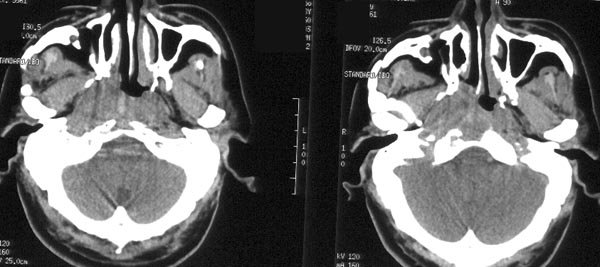

患者放疗后半年ct复查

ct平扫:鼻咽右侧壁增厚,右侧咽隐窝消失,右侧咽旁间隙变窄,但病灶较原片明显缩小。原片所见鼻咽顶壁、顶后壁、后壁增厚,现已基本恢复正常,原片见枕骨斜坡、蝶骨基底部骨质破坏,现亦已修复,为高密度骨质充填。颈深筋膜各间隙未见肿大淋巴结。

ct诊断:鼻咽癌放疗后,肿物较前片明显缩小,颅底骨质破坏基本修复。